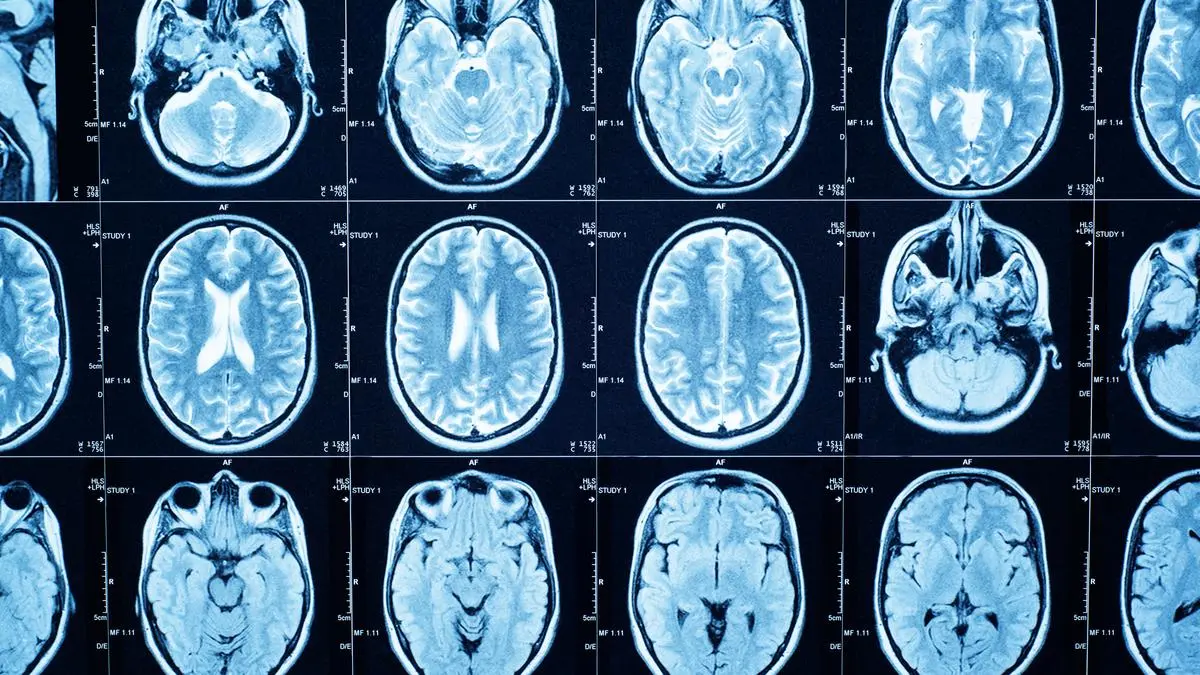

Wie sich unser Gehirn im Laufe unseres Lebens erneuert

Erwachsen sind wir, in Bezug auf unser Gehirn, erst mit etwas über 30 Jahren. Ganz grundsätzlich verläuft die Entwicklung unseres Gehirns in fünf Phasen – es ist ein ständiger Umbau im Gange.

Die Neuverdrahtung des Gehirns verläuft in fünf Phasen